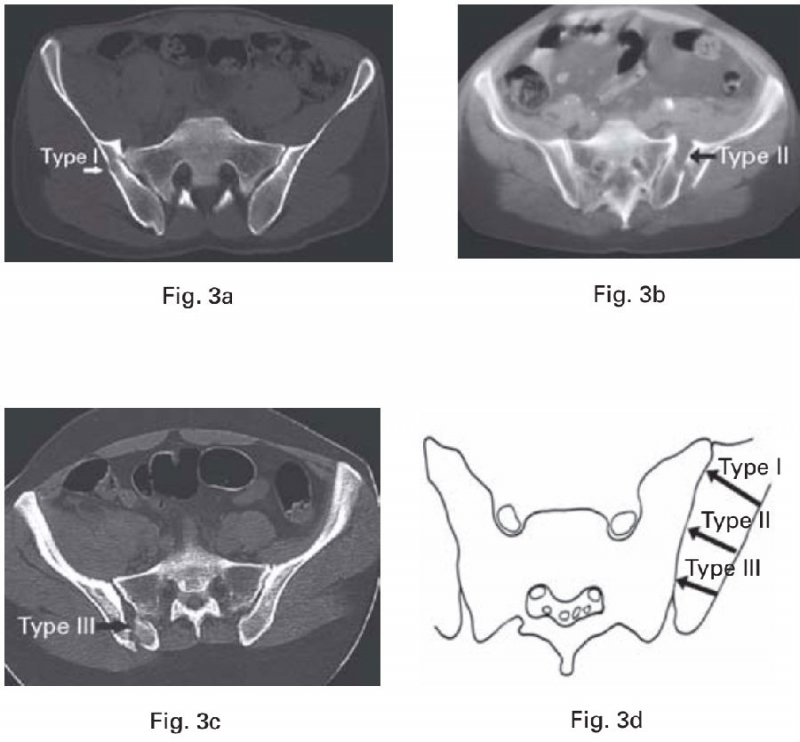

骶骨在骶髂关节水平主要有3道明显隆起的骨嵴,即骶骨耳状面前缘(骶骨翼)、骶骨耳状关节面后缘(骶骨侧嵴)和后方骶骨外侧嵴。我们通过总结65例新月形骨折患者的骨折特点发现,新月形骨折的髂骨骨折线进入骶髂关节的位置与骶骨上隆起的骨嵴及髂骨上相应的凹陷密切相关。

图4 骶骨侧方的3道骨嵴(红色虚线):①骶骨耳状面前缘(骶骨翼);②骶骨耳状关节面后缘(骶骨侧嵴);③后方骶骨外侧嵴。其中第①、②道骨嵴在侧方挤压应力作用下,可能起“支点”作用,第③道骨嵴大量韧带附着,其附近的骨折主要表现为髂骨内板的撕脱骨折。

新月形骨折病理解剖学分型以骶骨的骨性标志为分界,将新月形骨折分为三型:

Ⅰ型,新月形骨折线在骶骨翼水平进入骶髂关节;

Ⅱ型,新月形骨折线在骶骨侧嵴水平(真性骶髂关节面后界)进入骶髂关节;

Ⅲ型,新月形骨折线在骶骨侧嵴后方水平进入骶髂关节。

骶骨在骶髂关节水平主要有3道明显隆起的骨嵴,即骶骨耳状面前缘(骶骨翼),骶骨耳状关节面后缘(骶骨侧嵴),还有后方的骶骨外侧嵴。这些骨嵴与骶髂间的韧带如骶髂前韧带、骶髂骨间韧带、骶髂后韧带和髂腰韧带等相互作用,产生“核桃钳子”(Nutcracker)效应[7、8],即在侧方挤压暴力下,在骶髂偏前方产生压应力,而骶髂后方的韧带复合体产生张力。在侧方挤压暴力导致的骶髂偏前方的压应力作用下,偏前方的突出的骨嵴(骶骨翼、骶骨侧嵴)可能成为顶破相应髂骨处的支点。

另外,与骶骨突出的骨嵴相对应的是髂骨上的凹陷部分,则成为髂骨的相对薄弱点,从而更容易在此处产生髂骨的骨折,即新月形骨折解剖分型的Ⅰ、Ⅱ型。后方的骶骨外侧嵴则是通过强大的韧带结构和髂骨相连,在侧方挤压导致的骶髂后方张力作用下[8],更容易产生髂骨的撕脱骨折,即新月形骨折解剖分型的Ⅲ型。

通过CT轴位和冠状位多层面的观察,发现新月形骨折线通常出现在骶髂关节处,跟骶骨在骶髂相接部分突出的骨嵴和髂骨上的凹陷密切相关。骶骨在骶髂关节的骨嵴主要有三道,骶骨翼,骶骨侧嵴和后方的骶骨外侧嵴。其中骶髂关节中骶、髂骨质能紧密接触的主要是骶骨翼和骶骨侧嵴。这两处骨嵴在其对应的髂骨处均有相应的凹陷。